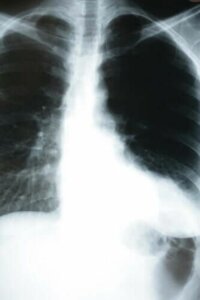

Zapalenie płuc jest infekcją, która atakuje pęcherzyki płucne. Są to mikroskopijnej wielkości struktury przypominające worki pokryte naczyniami krwionośnymi. Przeprowadzają one cały proces wymiany gazowej.

Innymi słowy, odpowiadają za wydalanie dwutlenku węgla (CO2) i wychwytywanie tlenu z powietrza dostarczanego z zewnątrz. Dlatego właśnie pytanie, w jaki sposób zapalenie płuc wpływa na nasz organizm, jest tak ważne – ponieważ ta wymiana gazów jest jednym z kluczowych procesów dla naszej egzystencji.